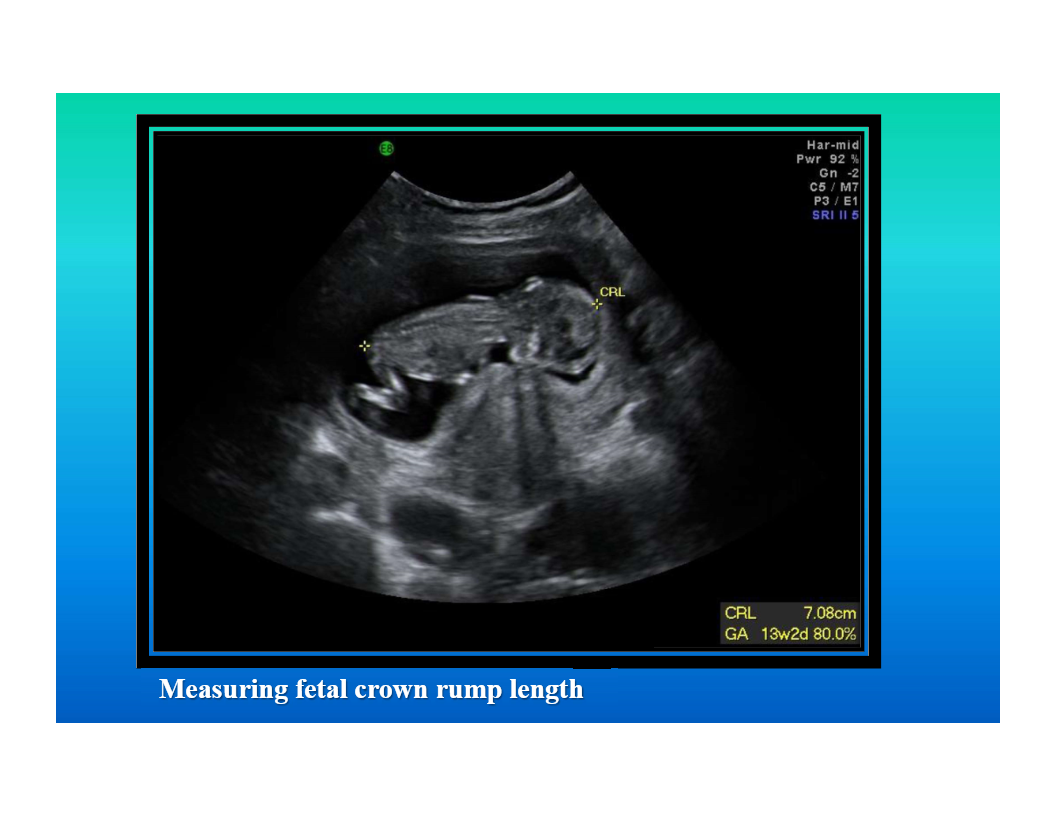

ultrasound

image based on computerized processing of sound

image descriptor is echogenicity

sound beam cannot pass through air

fluid is black

can be used in multiple areas of the body

good soft tissue differentiation

no known side effects

modality of choice for imaging pregnant woman